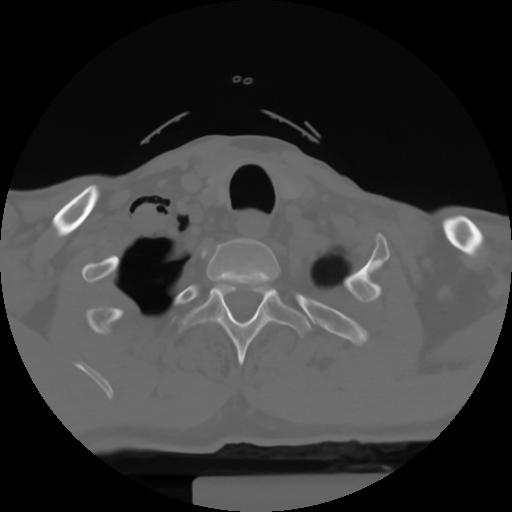

10 P.BLANDAS,,Axial,2.0,P.BLANDAS,,